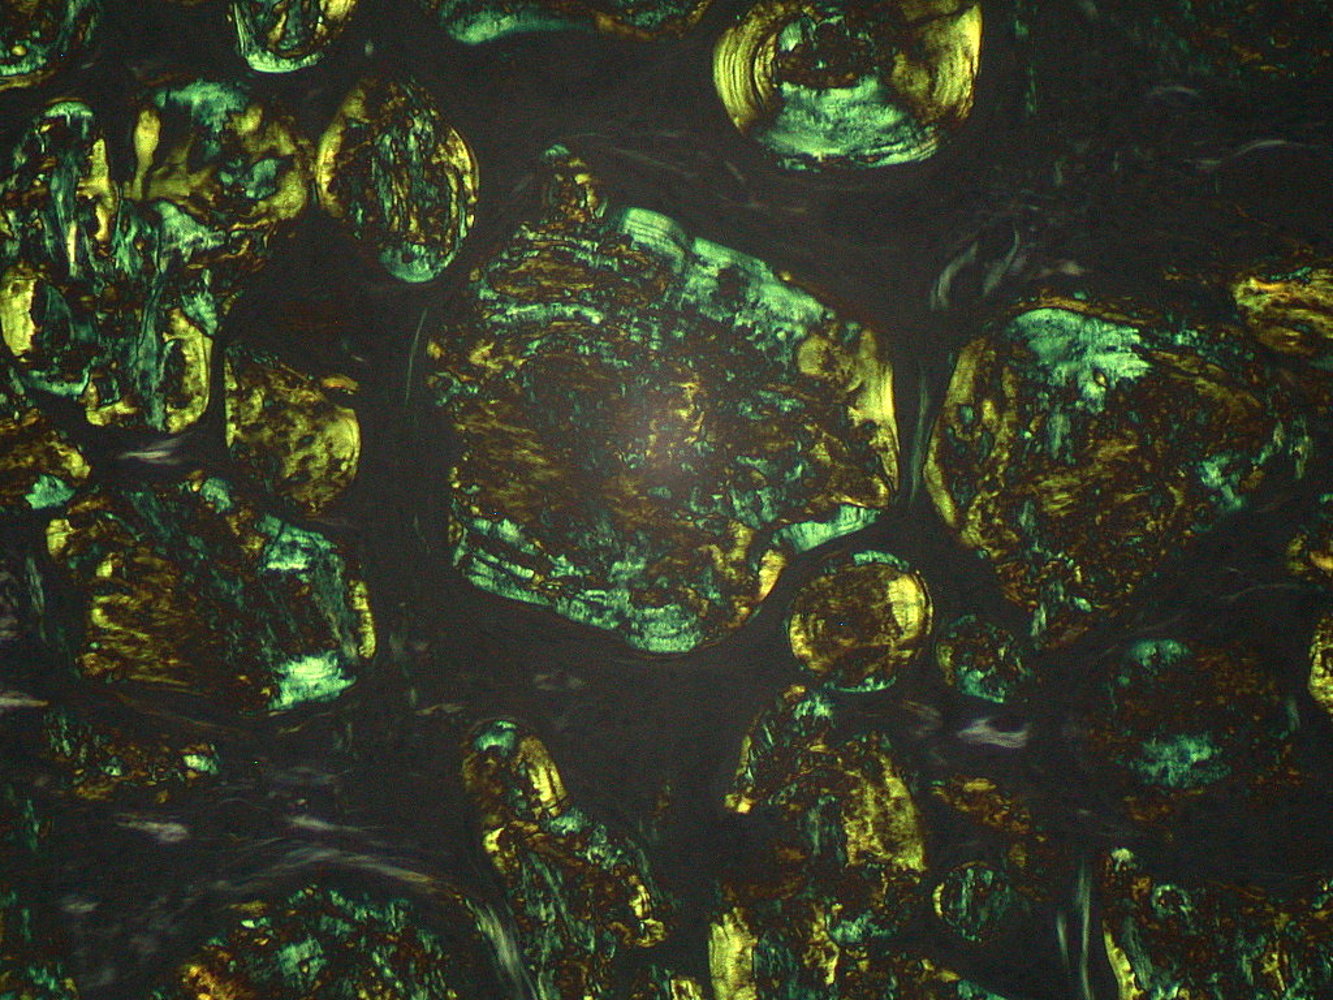

• Congo red stain to confirm amyloid deposition

• Pink to red appearance under nonpolarized light

• Apple-green birefringence under polarized light